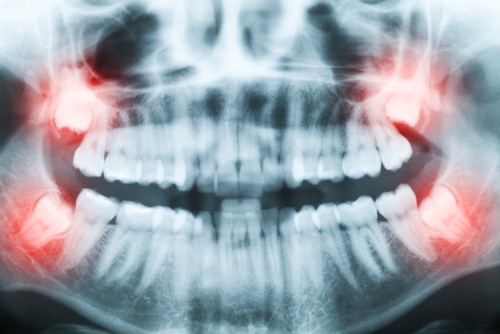

Let’s start with the basics. Wisdom teeth, or third molars, are a set of molars in the very back of the mouth. There are a total of four wisdom teeth, one in each quadrant of the mouth. They are also the last set of teeth to emerge. In fact, they usually do not emerge until 5 to 10 years after the rest of the permanent teeth emerge.

By the time they emerge, the patient already has a full set of functional teeth. Since wisdom teeth are also the largest teeth in the mouth, there is not always enough room inside the jaw for them. In other cases, there may be enough room, but they are growing in sideways rather than vertically, pushing against the second molars as they come through (more on this below).

Wisdom teeth that grow sideways or emerge when there is not enough space in the jaw can damage other teeth and gums. It can also make orthodontic treatment more challenging, which is why dentists typically recommend wisdom tooth extraction before orthodontic care.